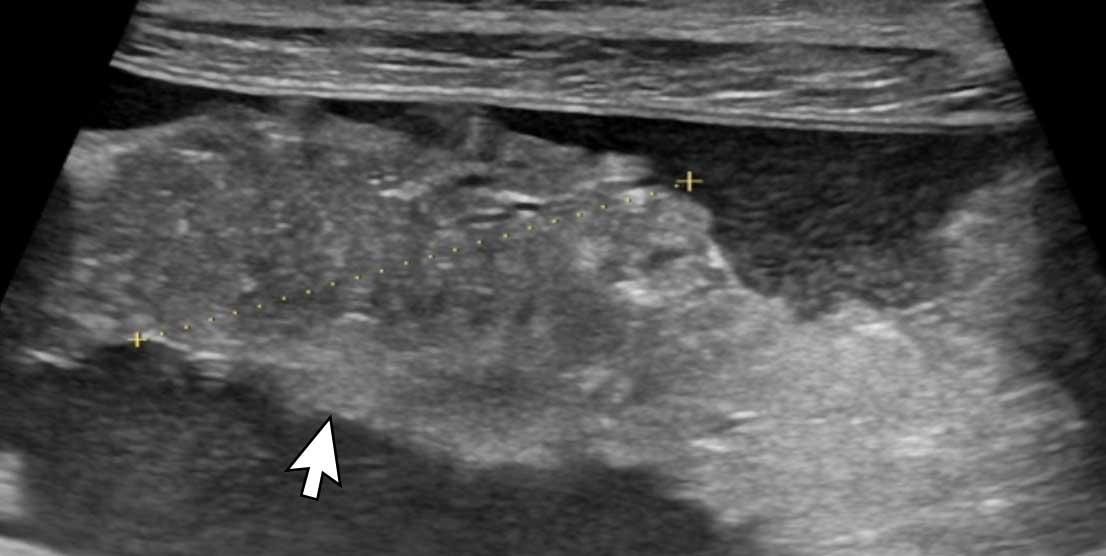

Hình ảnh

Hình ảnh siêu âm của một bệnh nhân nhập viện với cổ trướng (dấu hoa thị) cho thấy cả các nốt khối u trên phúc mạc thành (đầu mũi tên) lẫn một khối u lớn trên phúc mạc tạng (mũi tên trắng).